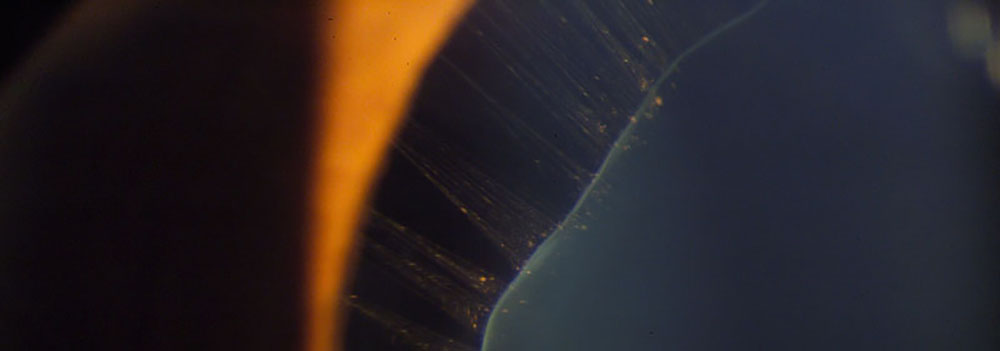

Luxación del Cristalino en Sindrome de Marfan. Fotografía, Instituto Barraquer de América